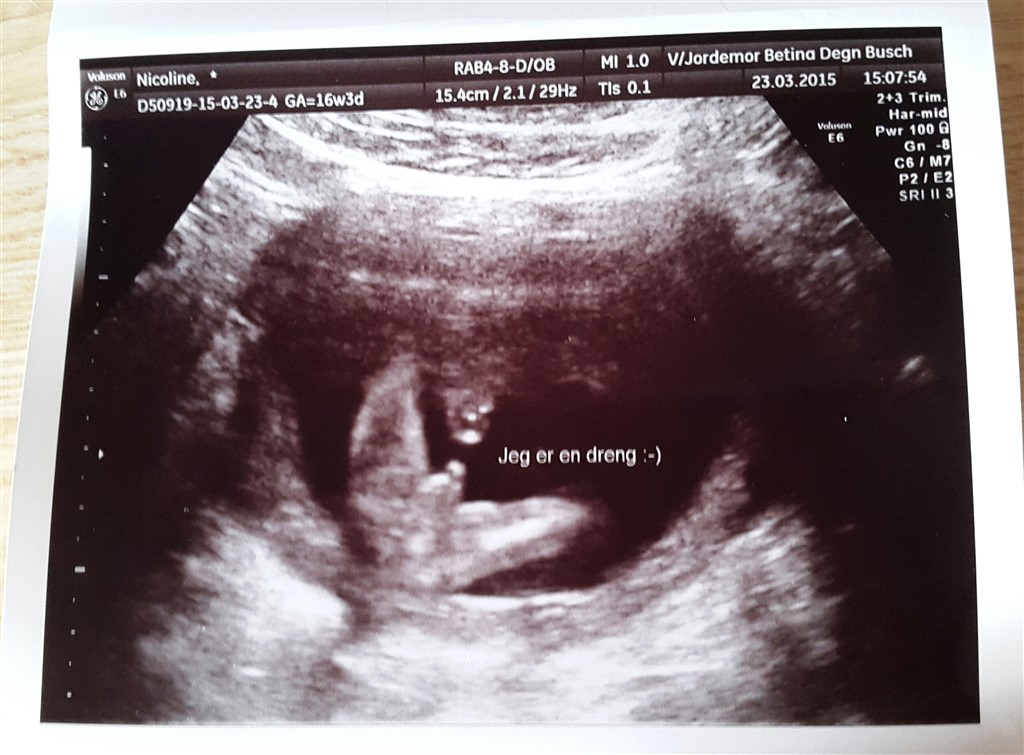

Vi venter vores første barn - er 28+1 I dag . . Da vi var til Nakkefoldscannning da jeg var 12+0 uger henne sagde vores scannings læge at vi ventede os en lille pige, men han ville ikke sige det med sikkerhed selvom han dog mente det 90% . . Da jeg var 16+3 havde vi lige brug for en tryghedsscanning som så endte med at blive en kønsscanning I stedet

. . Fik hende der scannede mig det mest perfekte billede på at det ikke var en pige som han mente til Nakkefoldscannningen, men at det er en lille dreng vi venter os

Vedhæftede fotos (klik for at se i fuld størrelse)